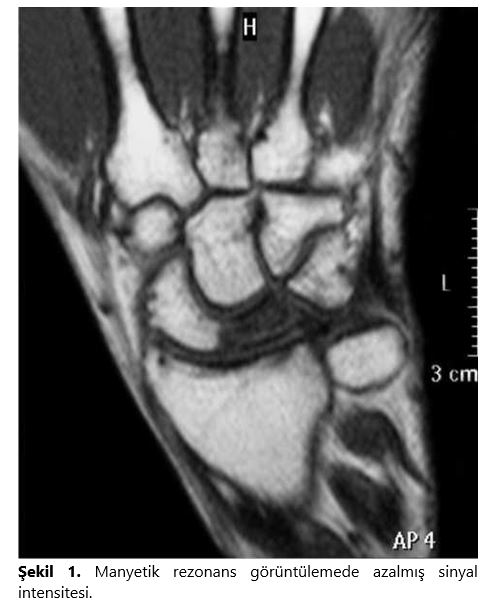

Direkt grafiler ulnar varyans, karpal yükseklik, radial inklinasyon ve dejeneratif değişikliklerin değerlendirilmesi açısından son derece önemlidir. Ulnar varyansın tam olarak değerlendirilmesi için omuz 90°, dirsek 90° ve önkolun nötral pozisyonda olması önemlidir. Hastalığın başlangıcında direkt grafiler tamamen normaldir, daha sonra lunatumda yaygın skleroz ortaya çıkar. Hastalığın ilerleyen dönemlerinde lunatumda çökme oluşur, bunu kapitatumun yukarıya yönlenmesi, skafoidin yer değiştirmesi ve sonrasında hızla gelişen yaygın artroz bulgularının ortaya çıkması takip eder. Manyetik rezonans görüntüleme (MRG) direkt radyolojik bulguların olmadığı hastalığın erken dönemlerinde etkilidir. Özellikle Ti ağırlıklı kesitlerde düşük sinyal intensiteleri, T2 ağırlıklı kesitlerde ise hiperintens görünüm izlenir (Şekil i).